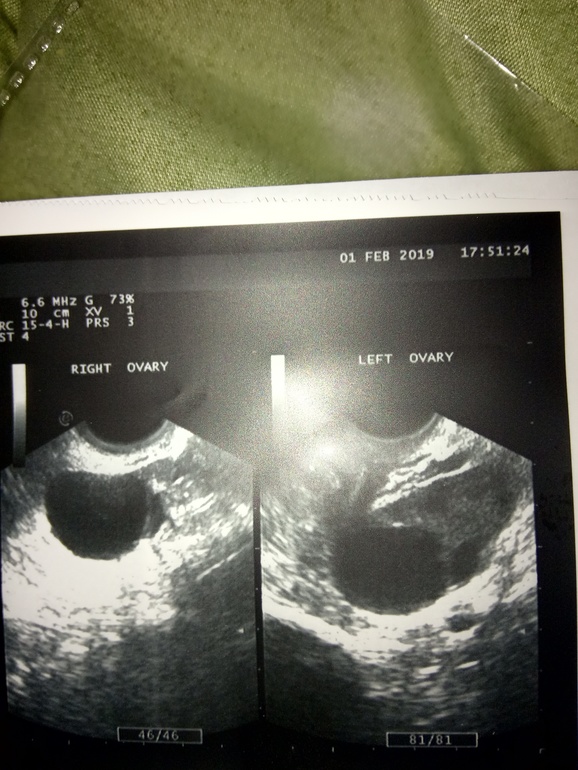

Сделала УЗИ сегодня...,ничего конкретно не понимаю. Груди болить ужасно,и ТТ 37.2

Персистенция в обоих я(((